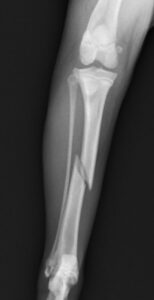

落下事故で右足の脛を骨折したワンちゃんが来院されました。ロッキングプレートであるMATRIX2.5と2.4スクリューで手術し、無事元気に歩いて退院していきました。よかったね。